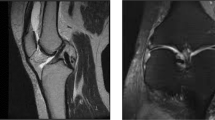

Following institutional review board approval, a retrospective cohort analysis was conducted on athletes treated for acetabular labral tears and their clinical courses of recovery. Primary outcomes of interest included performance/participation level defined as return to current level of competition per sport. Time to return to play was measured as days until next game competition was also documented.

Subjects included in this study participated in NCAA division 1 athletics at Virginia Polytechnic Institute and State University (VT). Both male and female patients, regardless of age, were included if they were categorized as student athletes in the electronic medical records (EMR) at Virginia Tech (2005–2020). The study included all major sports at the university (Table 1). A total of 47 patients were included in this study. All patients included in the cohort had a confirmatory MRI diagnosis of a hip labral tear as confirmed by musculoskeletal radiologist or included in the discussion of the primary surgeon. Specific location, characterization, or extent of the tear was not included for every patient and, therefore, was not evaluated as part of this study. This was a convenience sample selected based on the number of clinical cases available through the VT athletic medical records, which negated the need for exclusion criteria in this analysis. Athletes self-selected operative vs non-operative management based on a number of factors including in-season vs out of season injury, ability to participate in sport at a high-performance level, class year and eligibility (e.g. freshman vs senior) as well as other personal reasons. These results were not provided to subjects nor was any personal identifying information included in the study. All data is de-identified and was reported in aggregate fashion only. High-performance level of competition was defined in this study as participants being able to participate in game competition of their individual sporting event.

Records were reviewed using a keyword search for acetabular labral injuries, tears, and hip impingement including their respective rehabilitation processes and outcomes. All methods were performed in accordance with the relevant guidelines and regulations, and all identifying patient information was not included within the contents of this manuscript. Written informed consent was waived by the ethics committee of Virginia Tech as this was a retrospective chart review of patient data. Data was then collected and stored in a secure password-protected database (Microsoft Excel). Gender, age, sport, incident date, MRI impression, date of MRI, treatment (operative or non-operative), surgery date, and date of return to sport was included for each patient. Follow up intervals as well as discharge criteria outside of return to play and days lost from sport were not provided given the retrospective nature of this study.